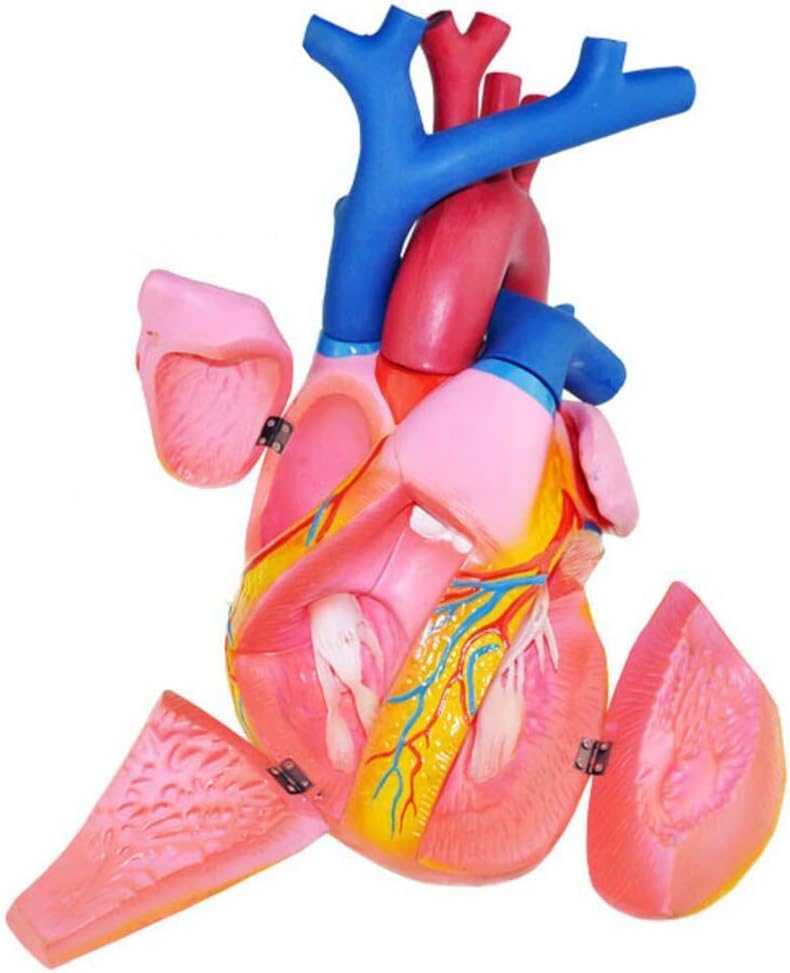

medical device

medical device